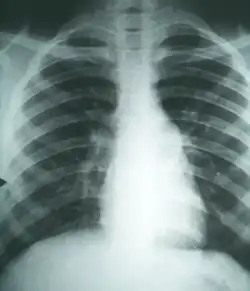

A case of pulmonary fibrosis caused by coccidioidomycosis

Coccidioidomycosis diagnosis relies on a combination of an infected person's signs and symptoms, findings on radiographic imaging, and laboratory results.[4] The disease is commonly misdiagnosed as bacterial community-acquired pneumonia.[4] The fungal infection can be demonstrated by microscopic detection of diagnostic cells in body fluids, exudates, sputum and biopsy tissue by methods of Papanicolaou or Grocott's methenamine silver staining. These stains can demonstrate spherules and surrounding inflammation.

Imaging

Chest X-rays rarely demonstrate lung nodules or cavities. These images commonly demonstrate lung opacification, pleural effusions, or enlargement of lymph nodes associated with the lungs.[4] Computed tomography scans of the chest are more sensitive than chest X-rays to detect these changes.[4]